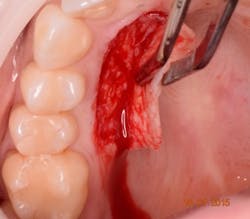

The harvesting technique (figure 4) should aim for a graft thickness between 1-3 mm and be 15-25% larger than the desired final size. Harvesting a larger amount of graft is warranted due to both initial (immediate) and secondary contraction of the graft during healing. A thin graft will have less primary and more secondary contraction, where as a thick gingival graft will have more primary and less secondary contraction. In general, a harvested soft-tissue graft can be expected to shrink on average of 15% to 20%.